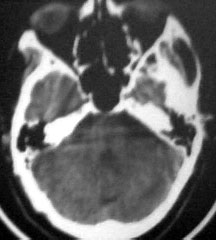

病人男性52岁,一年前曾患脑出血.今突发剧烈头痛,恶心,呕吐..病人家属说病人自去年脑出血以后,精神异常!请大家看看左侧颞叶病灶考虑什么?片子不是很清楚请大家见谅!!左颞叶病灶ct值最高处为85hu

左侧颞叶海马回钩部斑片状高密度致密影,考虑:出血.

病人此次症状应与右侧丘脑及基底节出血破溃入脑室有关。

左颞叶病灶我认为不是出血,就算是出血,也与右侧病灶性质不同。理由:1.该病灶密度较淡而不均匀,其间见斑点状更高密度。急性出血,应该不会是这个样子。

2.病灶对周围无推移挤压迹象,也无水肿。倒是病灶旁边、左侧环池局部扩张,与右侧病灶

完全不一样。

综合上诉特点,左颞叶病灶我首先考虑:avm。

左侧颞叶考虑血管畸形,右侧丘脑及基底节出血破溃入脑室